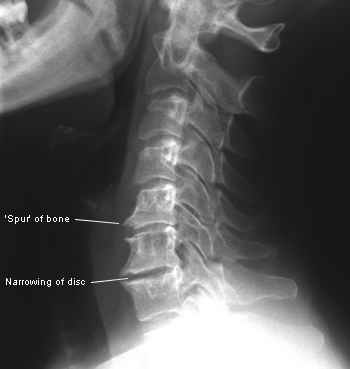

As chiropractors, when we help someone with their arthritis pain, we start with our examination process. Our exams include orthopedic, neurological, and physical exam tests, as well as any necessary X-rays or MRI. When you look at the X-ray or MRI you’re going to see things like degeneration of the cartilage, as well as the growth of bone spurs, which are called osteophytes. Osteophytes are bones spurs that form around the joint because it is not moving properly and the body is trying to fuse itself together.